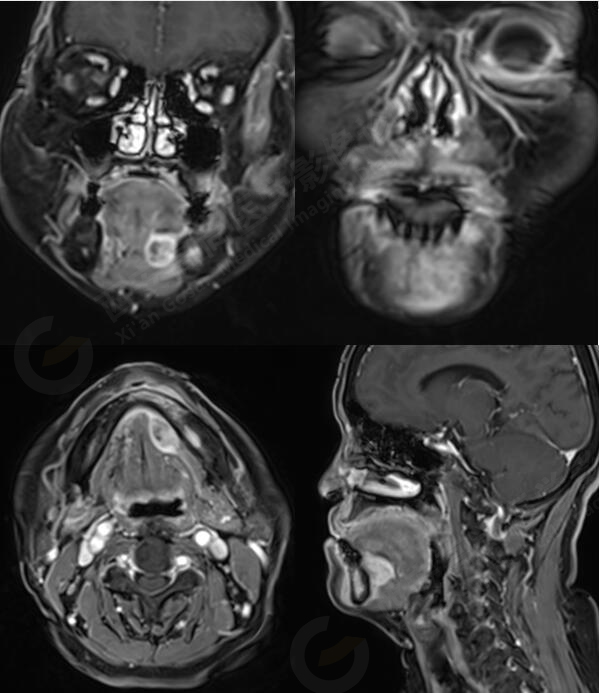

MR平掃+增強(qiáng):左側(cè)口底部下頜骨周圍見大小約3.4cmX3.3cmX3.3cm的團(tuán)塊狀稍長(zhǎng)T1稍長(zhǎng)T2信號(hào),壓脂像上呈稍高信號(hào),病灶邊緣清晰,形態(tài)不規(guī)則,下頜骨骨質(zhì)破壞,強(qiáng)化掃描示:左側(cè)下頜骨周圍病灶呈不均勻明顯強(qiáng)化,邊緣強(qiáng)化為著。

左側(cè)口底部下頜骨周圍占位,鱗Ca可能。

此腫瘤位于左側(cè)口底部下頜骨周圍,未見明顯囊變,下頜骨骨質(zhì)破壞,DWI像上病灶呈明顯低信號(hào),ADC圖上呈低信號(hào),增強(qiáng)后不均勻明顯強(qiáng)化,病人年齡較大,可以考慮惡性腫瘤,口底好發(fā)鱗癌。